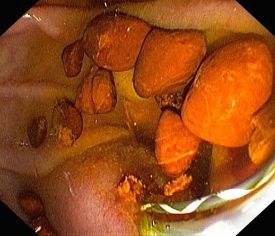

- Entfernung von Gallensteinen, mechanische Steinzertrümmerung (Lithotrypsie)

Die Untersuchung wird in Bauchlage durchgeführt. Aus Sicht des Patienten ähnelt sie der Magenspiegelung, allerdings wird das Endoskop tiefer in den Zwölffingerdarm platziert, so dass die Gallengangsmündung (Papille) zu sehen ist. In diese wird Kontrastmittel eingespritzt, und so die Gallengänge unter Röntgendurchleuchtung sichtbar gemacht. Ist beispielsweise ein Abflusshindernis in den Gängen durch Gallensteine vorhanden, kann dies nun endoskopisch mit verschiedenen Methoden beseitigt werden.